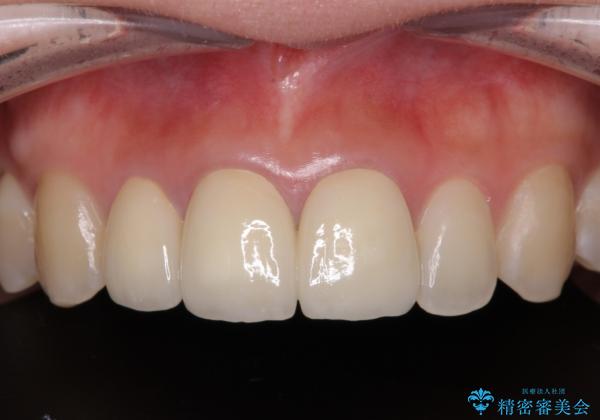

前歯の黒い縁を綺麗にしたい 前歯のオールセラミック

- 以前に装着した前歯のクラウンの縁が見えていることを気にして来院された患者様です。

根尖部に病変のある2歯は事前に根管治療を行い、オールセラミッククラウンにて補綴することとしました。

金属を除去したことで、周りと調和した自然な色合いとなり、クラウンの際の位置も歯肉に少し入り込む位置となっているためまるで本物の歯のような仕上がりとなりました。